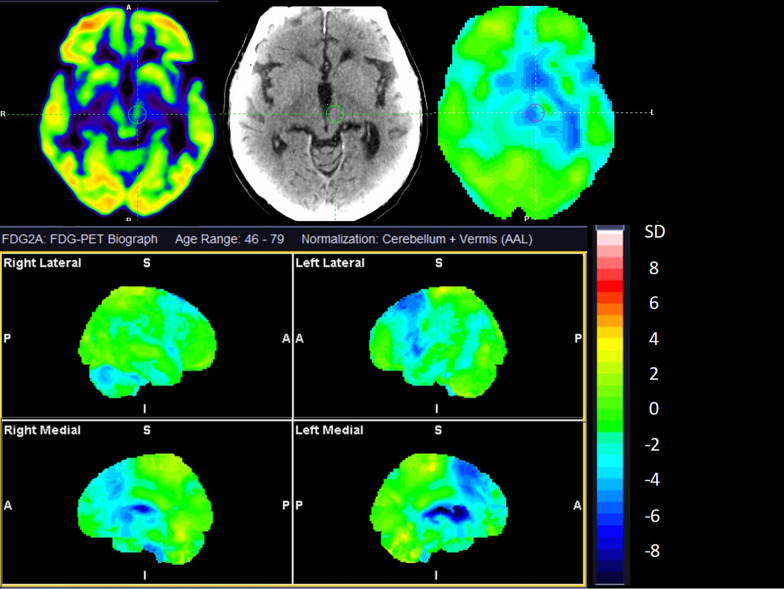

We used Scenium, SyngoVia (Siemens Healthineers, Erlangen, Germany) to analyse the images of the included patients. A nuclear medicine specialist with more than 10 years of experience in PET neuroimaging (LM) classified the scans as MSA-C, MSA-P, CBD, PSP, DLB, or non-AP, based on previously published disease-specific [18F]FDG features [ref. 18]. Briefly, a reduced [18F]FDG uptake in the cerebellum would suggest a potential diagnosis of MSA-C. MSA-P was considered when there was a symmetric or slightly asymmetric reduction in activity uptake in the posterior putamen. This suspicion was strengthened if both the posterior putamen and cerebellum showed decreased activity uptake with an absence of cortical involvement. CBD was considered if an asymmetrical reduction in frontoparietal activity was observed, alongside involvement of the ipsilateral basal ganglia and mesencephalon. For PSP, a more symmetrical reduction in activity uptake in the mesial and lateral frontal cortex, basal ganglia, and particularly the mesencephalon was indicative. DLB was typically characterized by a reduction in parietotemporooccipital activity uptake, along with the presence of a cingulate island sign. The reader was blinded to all clinical information during the classification process except for previous neuroimaging, if available. Thus, MRI scans and results from dopamine transporter imaging were visually interpreted without access to clinical data and used for reading of the [18F]FDG PET. In cases of uncertainty regarding the classification of scans, the nuclear medicine specialist would make a decision based on the best professional judgment to prevent any instances of missing data.